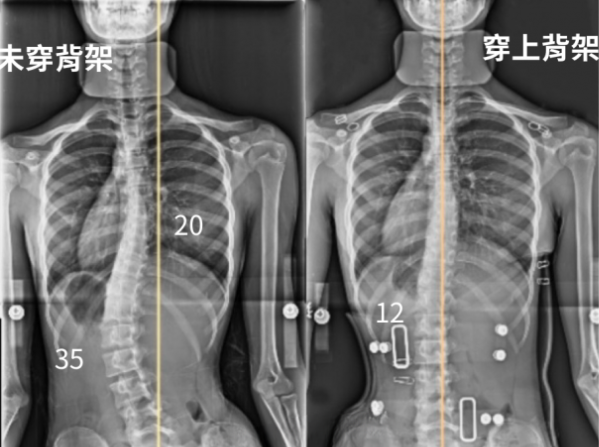

12歲女生,背架X光對比:沒穿背架時,體態明顯偏左,肩膀左低右高;穿上Schroth(施羅斯)背架後,脊椎明顯變直,頭、骨盆和脊椎回到同一條垂直中心線,體態回正。